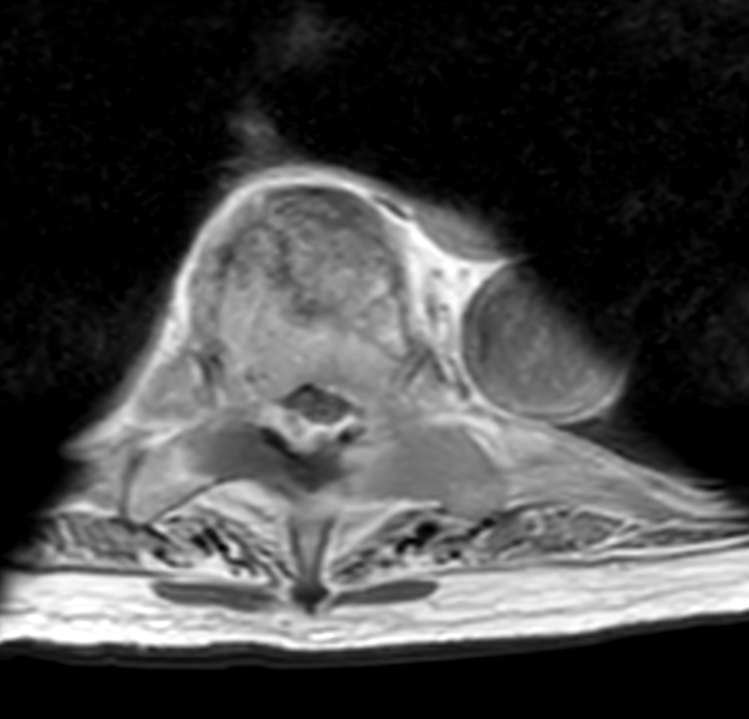

Axial T2w TSE (T4)